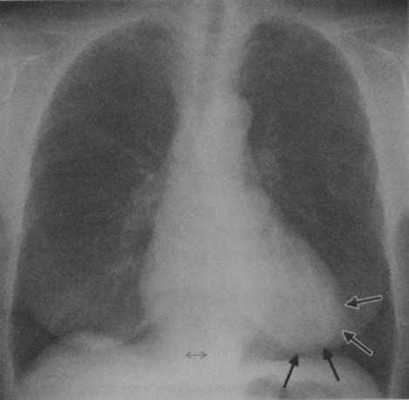

АГ у женщины 63 лет. Рентгенография грудной клеткив прямой проекции демонстрирует сужение талии сердцас приподнятой верхушкой(стрелки) в связи с гипертрофией миокарда.

Та же пациентка, что и на рисунке 6.1. МРТ. SSFP-изображение на четырехкамерном срезе демонстрирует выраженную гипертрофию миокарда ЛЖ, преимущественно перегородки.